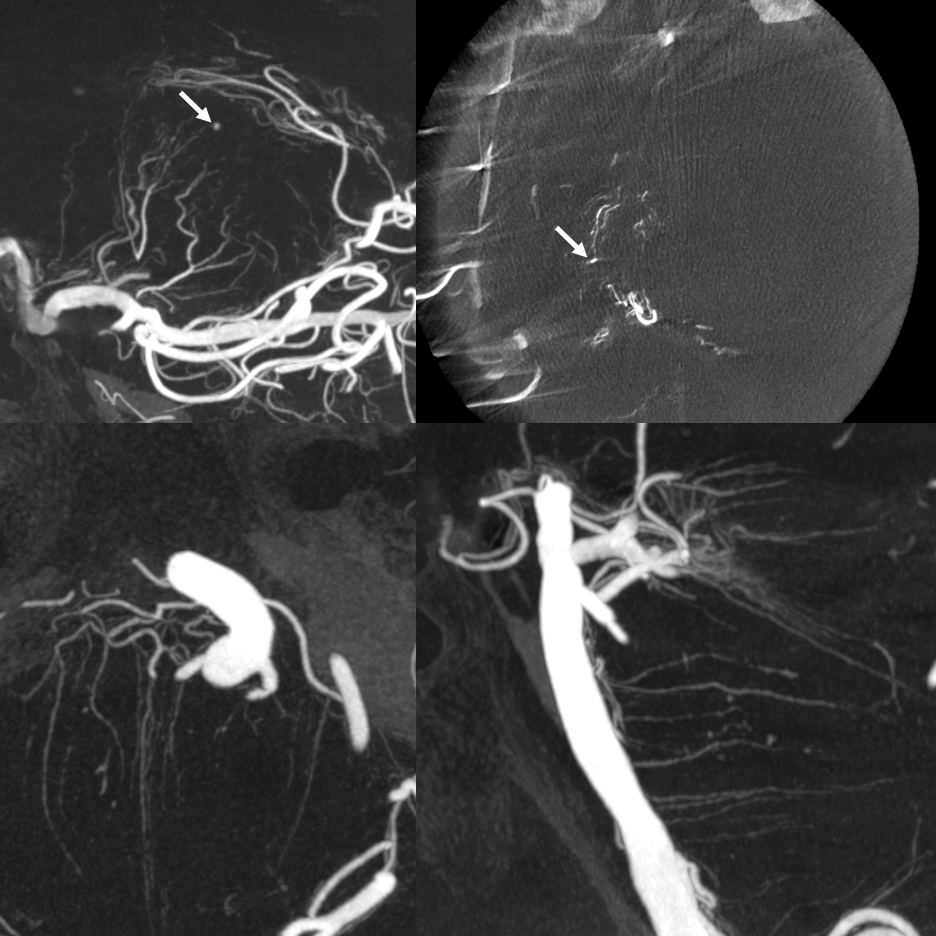

Finally came across something that might pass for them — history is angiography for evaluation of cerebellar hemorrhage

Flat Panel imaging

Good luck seeing these on angio

Can you maybe see on this stereo?

Here they are…